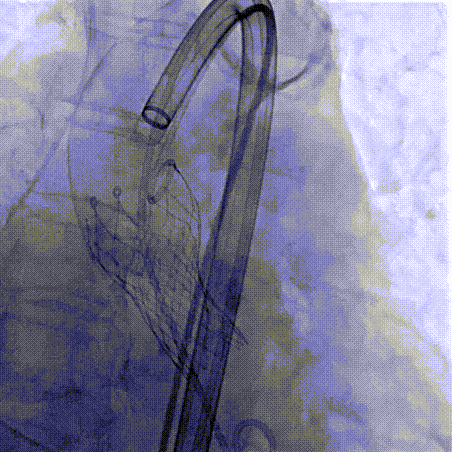

Step 1.升主动脉情况评估

Step 2.建立大鞘通路:大鞘通过升主、边进入边加弯,避免剐蹭弓部斑块